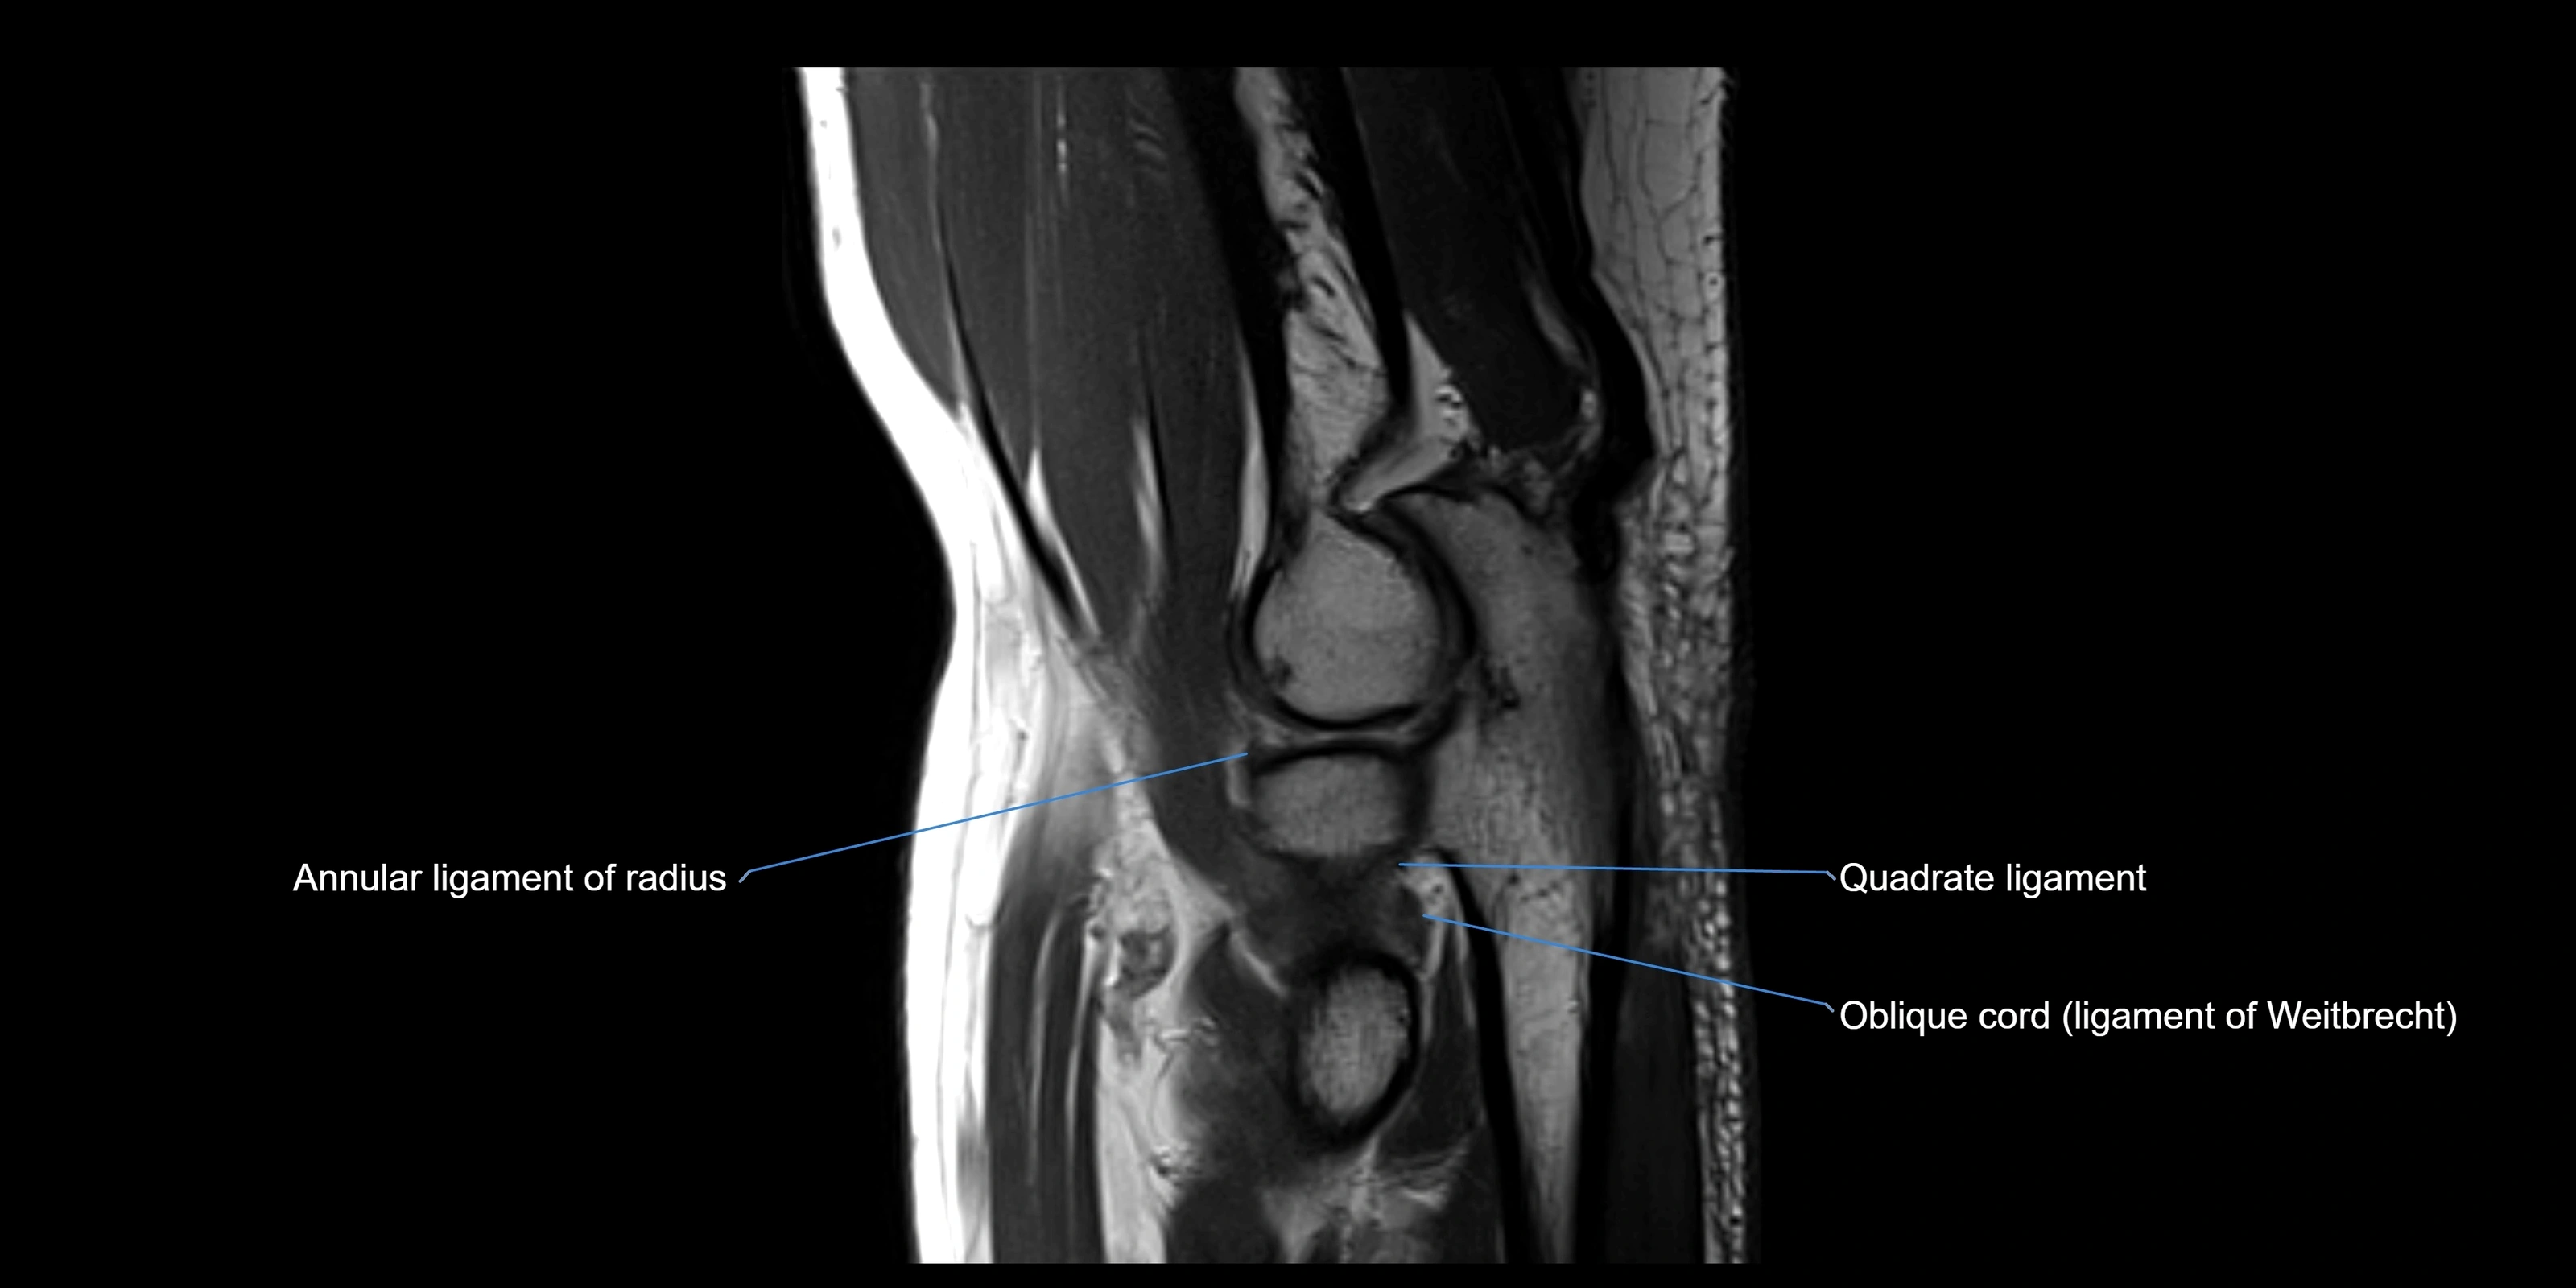

STIR:

• Normal ligament: dark band encircling radial head.

• Pathology: bright hyperintense periligamentous signal suggesting edema, sprain, or partial tear.

Proton Density Fat-Saturated (PD FS):

• Normal: dark, well-defined band outlining the radial head.

• Partial tear: irregular or bright hyperintense signal within or adjacent to ligament fibers.

• Joint effusion and reactive synovitis appear bright and are well visualized.

MRI images

image